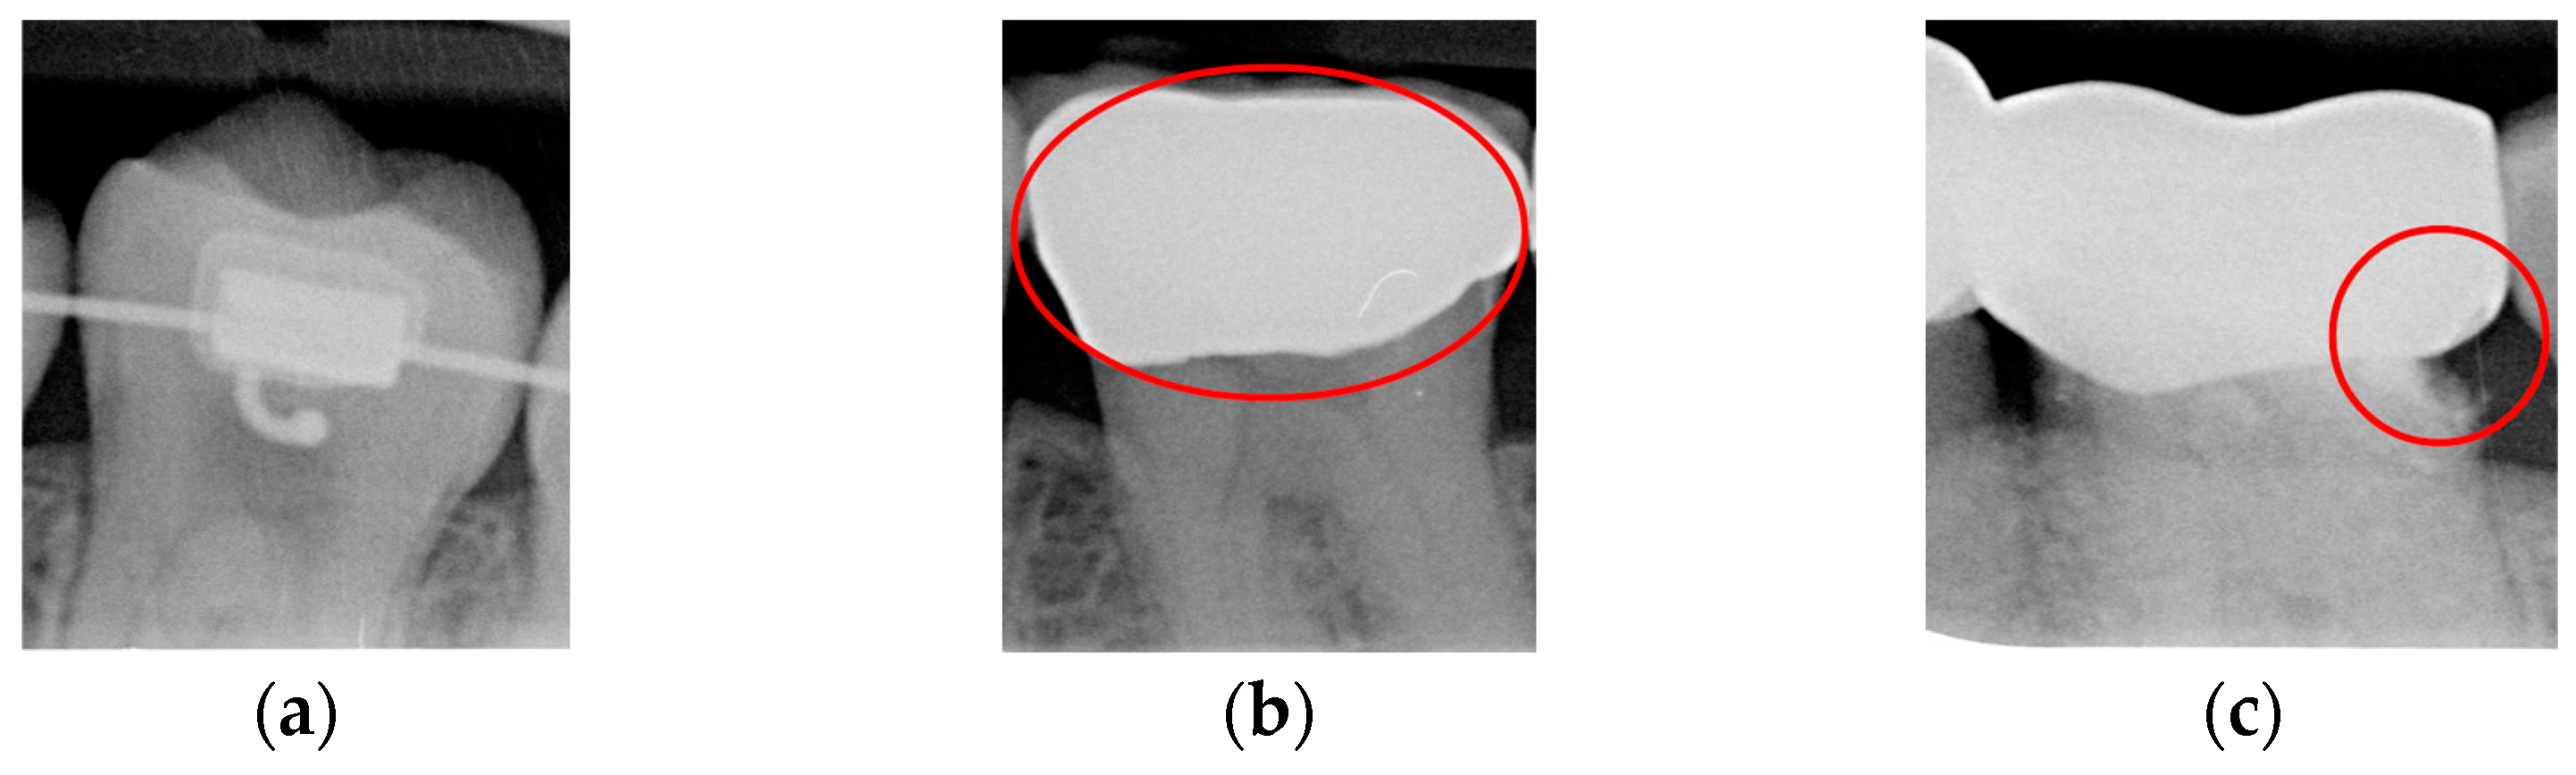

- Single-tooth extraction algorithm

A complete BW varies due to factors such as angle, exposure size, the number of teeth, and interproximal spacing. Using fixed parameters and thresholds can lead to misjudgments and low segmentation efficiency. To enhance flexibility and operability, the algorithm uses adaptive thresholds tailored to each BW based on brightness, size, and the number of teeth. Each BW is pre-processed before segmentation due to variations in mouth shape, tooth shape, and imaging angle. This study first applies to a gaussian high-pass filter to eliminate noise, reducing segmentation errors. Next, the images undergo binarization and erosion techniques to clarify background contours, making them easier to distinguish, as illustrated in Figure 3.

Figure 3.

BW image preprocessing. (a) Original BW. (b) Gaussian filter. (c) Horizontal erosion after binarization.

Due to angular issues in a BW, horizontal and vertical lines may not fully separate the teeth. This study addresses this by rotating and binarizing images multiple times to enhance the contrast between teeth and gaps. High-contrast images allow for accurate identification of tooth gaps through pixel horizontal projection as shown in Figure 4a. The image is divided horizontally into three parts, masking the upper and lower sections to focus on the middle, like the upper and lower sides of the red box in Figure 4b are masked. The valleys of the projection line in this region are identified as the x-minimum value, and the y-coordinate of the valley represents the vertical height separating the upper and lower rows of teeth after rotation. Additionally, during each rotation, a projection is made to identify the trough position in the middle of the image. The trough values (x-minimum) at each angle are compared to determining the optimal rotation angle for horizontal segmentation. Initially, the image is rotated within a range of plus or minus 15 degrees, in increments of 5 degrees. By comparing the trough values at each angle, the most suitable rotation angle for horizontal cutting is identified, as shown in Figure 4b.

Figure 4.

Horizontal projection of the rotated image. (a) BW rotated +5 degrees; (b) BW rotated +10 degrees.

According to Table 1. After performing small-angle rotations and comparing the trough values at each angle, it was determined that the lowest trough value (x = 36) occurs at a rotation of 11 degrees, which is lower than the trough value (x = 40) obtained at the initial rotation of 10 degrees. Therefore, it can be concluded that a positive 11 degrees is the most suitable rotation angle for this BW, which is more favorable for subsequent horizontal segmentation. If a smaller rotation angle is used from the beginning to find a suitable angle, multiple calculations will be required within the same range of angles. However, by gradually rotating the image in two steps, one large angle (5 degrees) and one small angle (1 degree) to obtain the most suitable rotation angle, we achieve the same result and find out the suitable angle more quickly. After rotating the image of each BW to a suitable angle, the height of the trough (y-value) is found. The height of the plumb coordinates of the troughs are found and the horizontal line separating the upper and lower jaws is plotted using the height of these coordinates. This allows the entire BW to be divided into upper and lower rows of teeth; the specific segmentation result is shown in Figure 5.